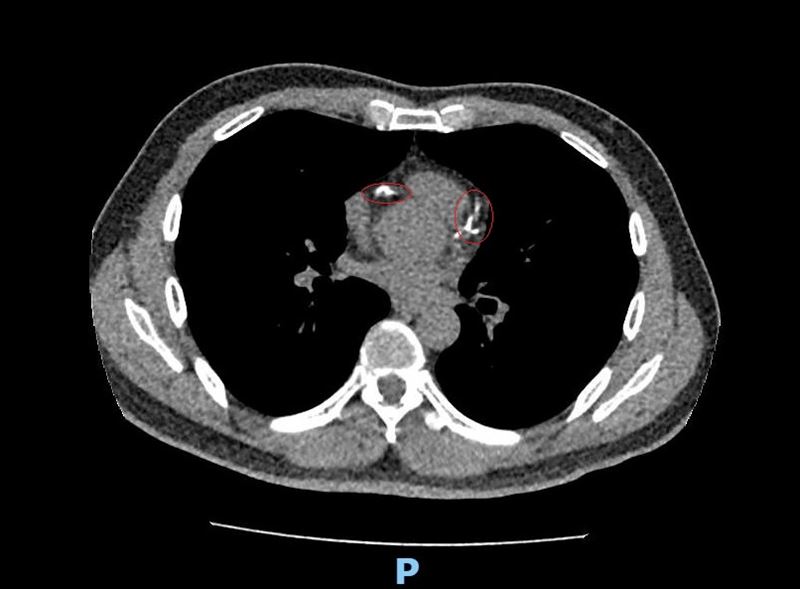

李學林表示,49歲林姓男子日前接受肺癌篩檢(LDCT),意外發現心血管鈣化,但無法確認是血管內或血管外鈣化,考慮到患者平時已出現胸悶症狀,進一步做心臟冠狀動脈電腦斷層,確認為3條主要冠狀動脈血管內鈣化狹窄達85%以上,若未及時處理,隨時可能引發急性心肌梗塞。

李學林指出,醫療團隊透過心導管手術搭配血管內震波碎石術(IVL),利用震波氣球貼近血管壁發出超聲壓力波,擊碎血管壁的堅硬鈣化斑塊,使原本僵硬的血管恢復擴張性,為支架放置創造理想的環境,再植入3支支架,使其完整展開、貼合血管,降低支架血栓及再狹窄風險。